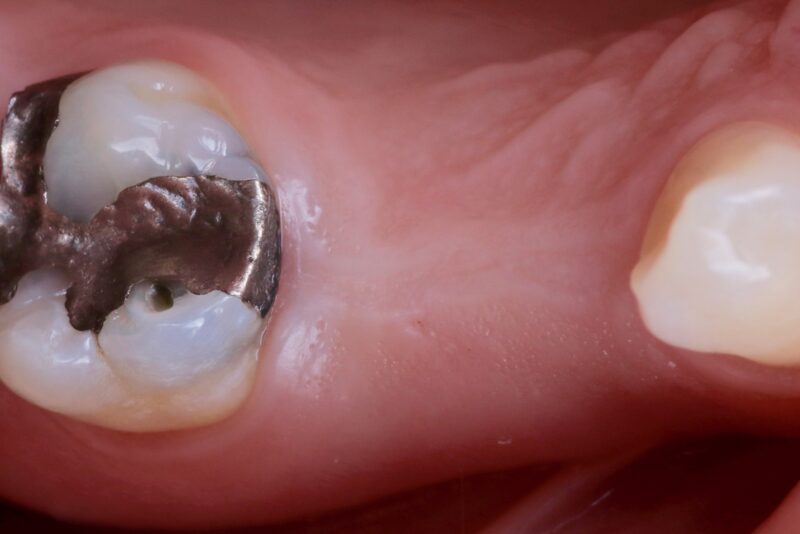

Looking back at a case I did a few years ago, I’ve realized how much my approach has evolved.

I placed two implants in the posterior region using guided surgery. At the time, I chose a tissue punch technique because there was plenty of keratinized tissue, and it felt like the most minimally invasive option. The implants healed well, and the…

Thanks for the reflection man. l am the same, I used to do more punches as well.

Although this case in particular looks like there is loads of tissue! So I still might be lazy lol